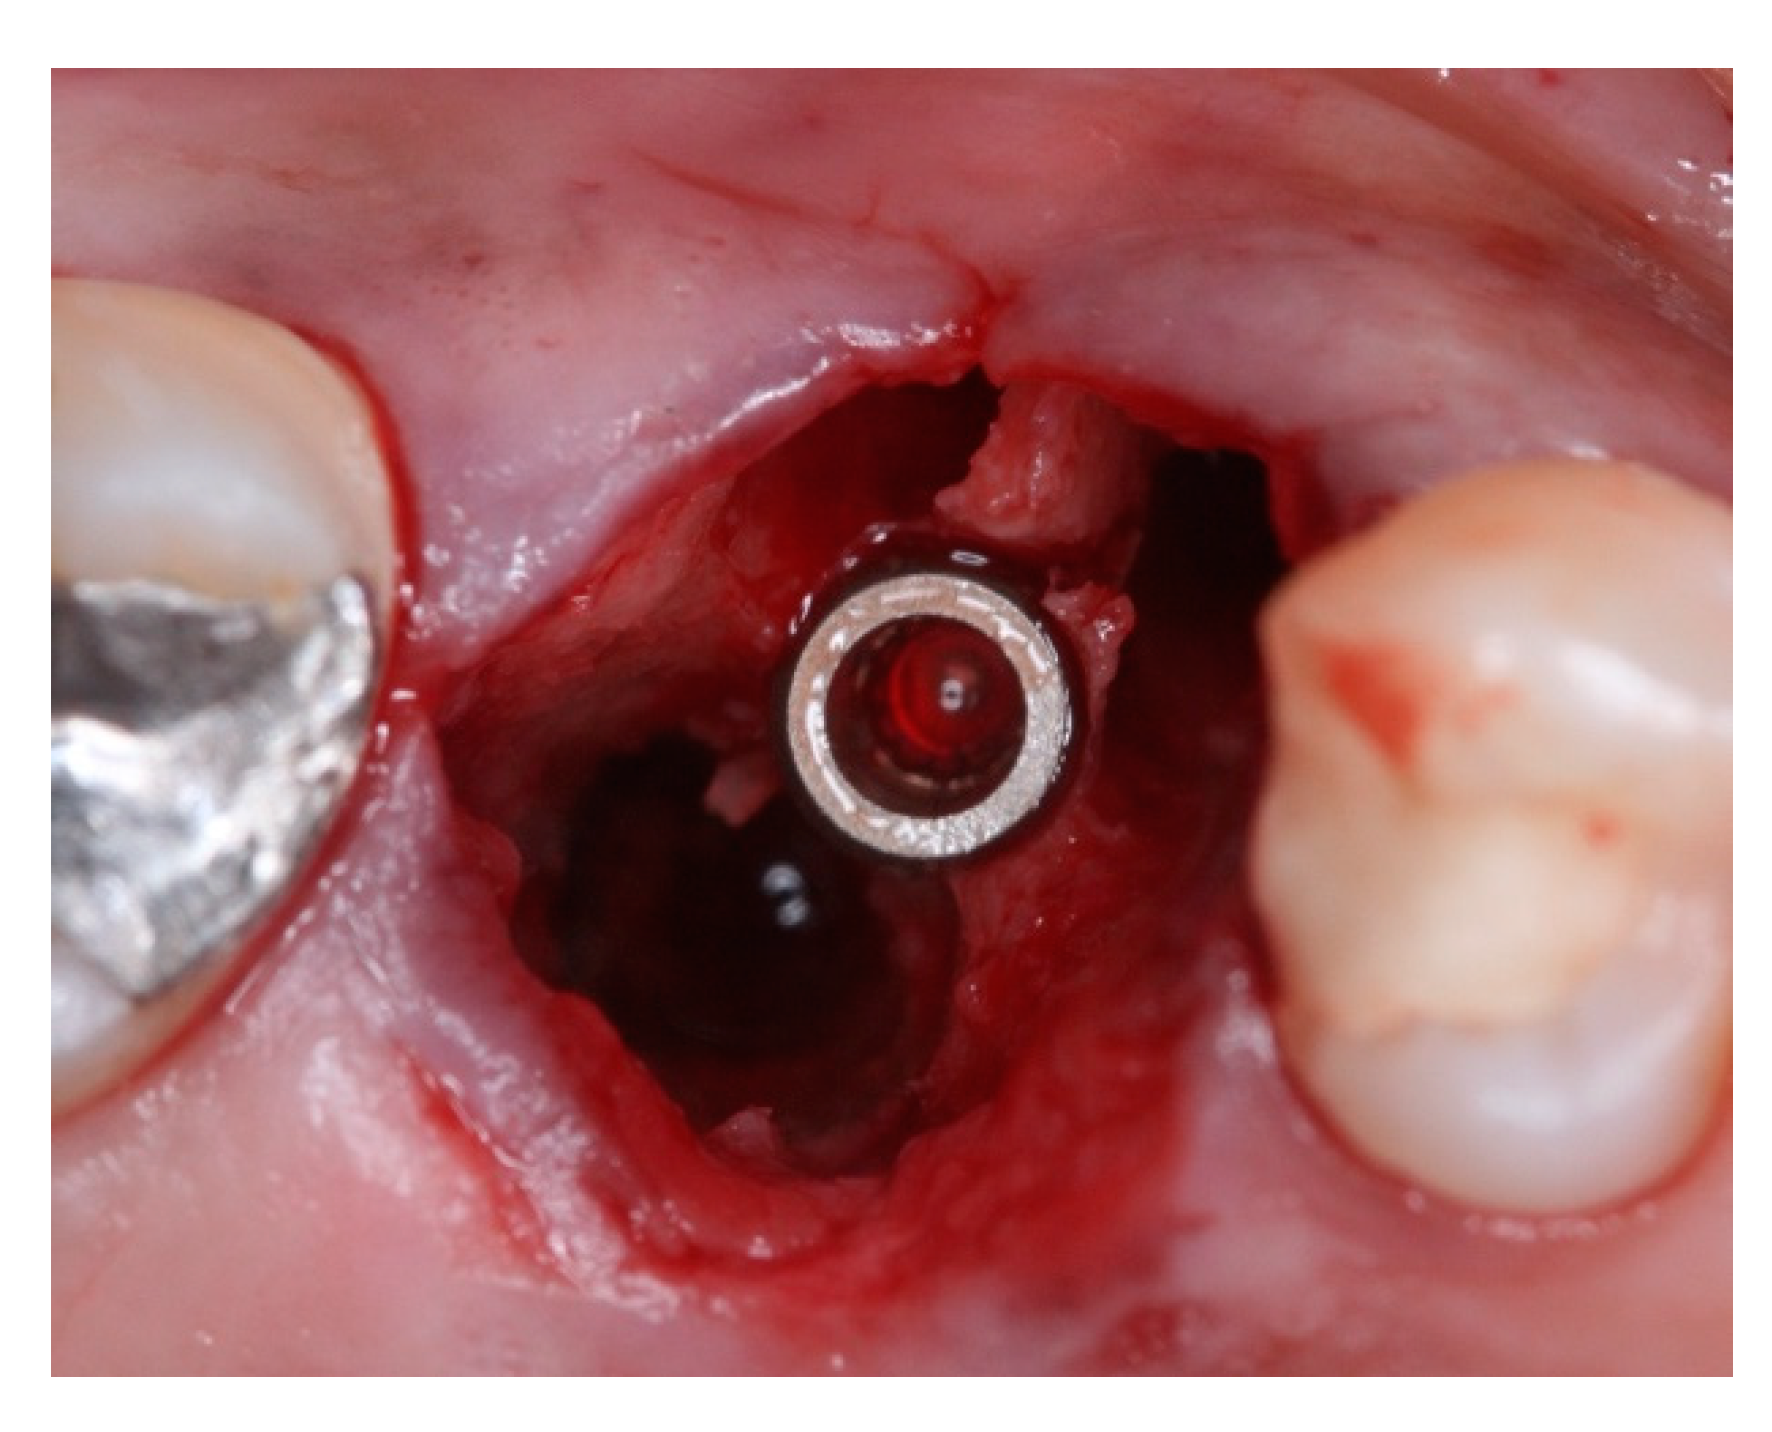

2. Materials and Methods